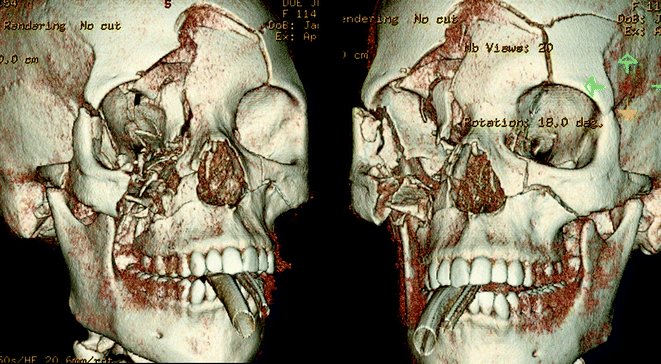

Fig. 19.7

Right frontotemporoparietal craniectomy (11 cm × 14 cm) with a left frontal EVD in place. The posterior extension stopped at a fracture line within the parietal bone and further removal of bone was not thought to be necessary at the time. The craniectomy extended inferiorly to the floor of the middle cranial fossa with less than a centimeter of temporal squamosal bone remaining

Fig. 19.8

A 27-year-old male deployed overseas suffered a gunshot wound to the head from an unknown caliber weapon. He underwent an emergent cricothyroidostomy and was transferred to higher level care with an admission GCS score of 8T. Initial head CT demonstrated significant right maxillary, orbital, frontal, and zygomatic fractures, retained metal fragmentation within the right frontal lobe and effacement of the frontal horn of the right lateral ventricle. A left frontal EVD was placed but within 24 h his ICPs were refractory to medical management. He underwent a right unilateral craniectomy in theater. He was transferred back to Walter Reed for further care and rehabilitation. One month after the accident he was discharged to neuro-rehab with a GCS 14 and moderate impairment in judgment and insight. He underwent cranioplasty 6 months after the injury.